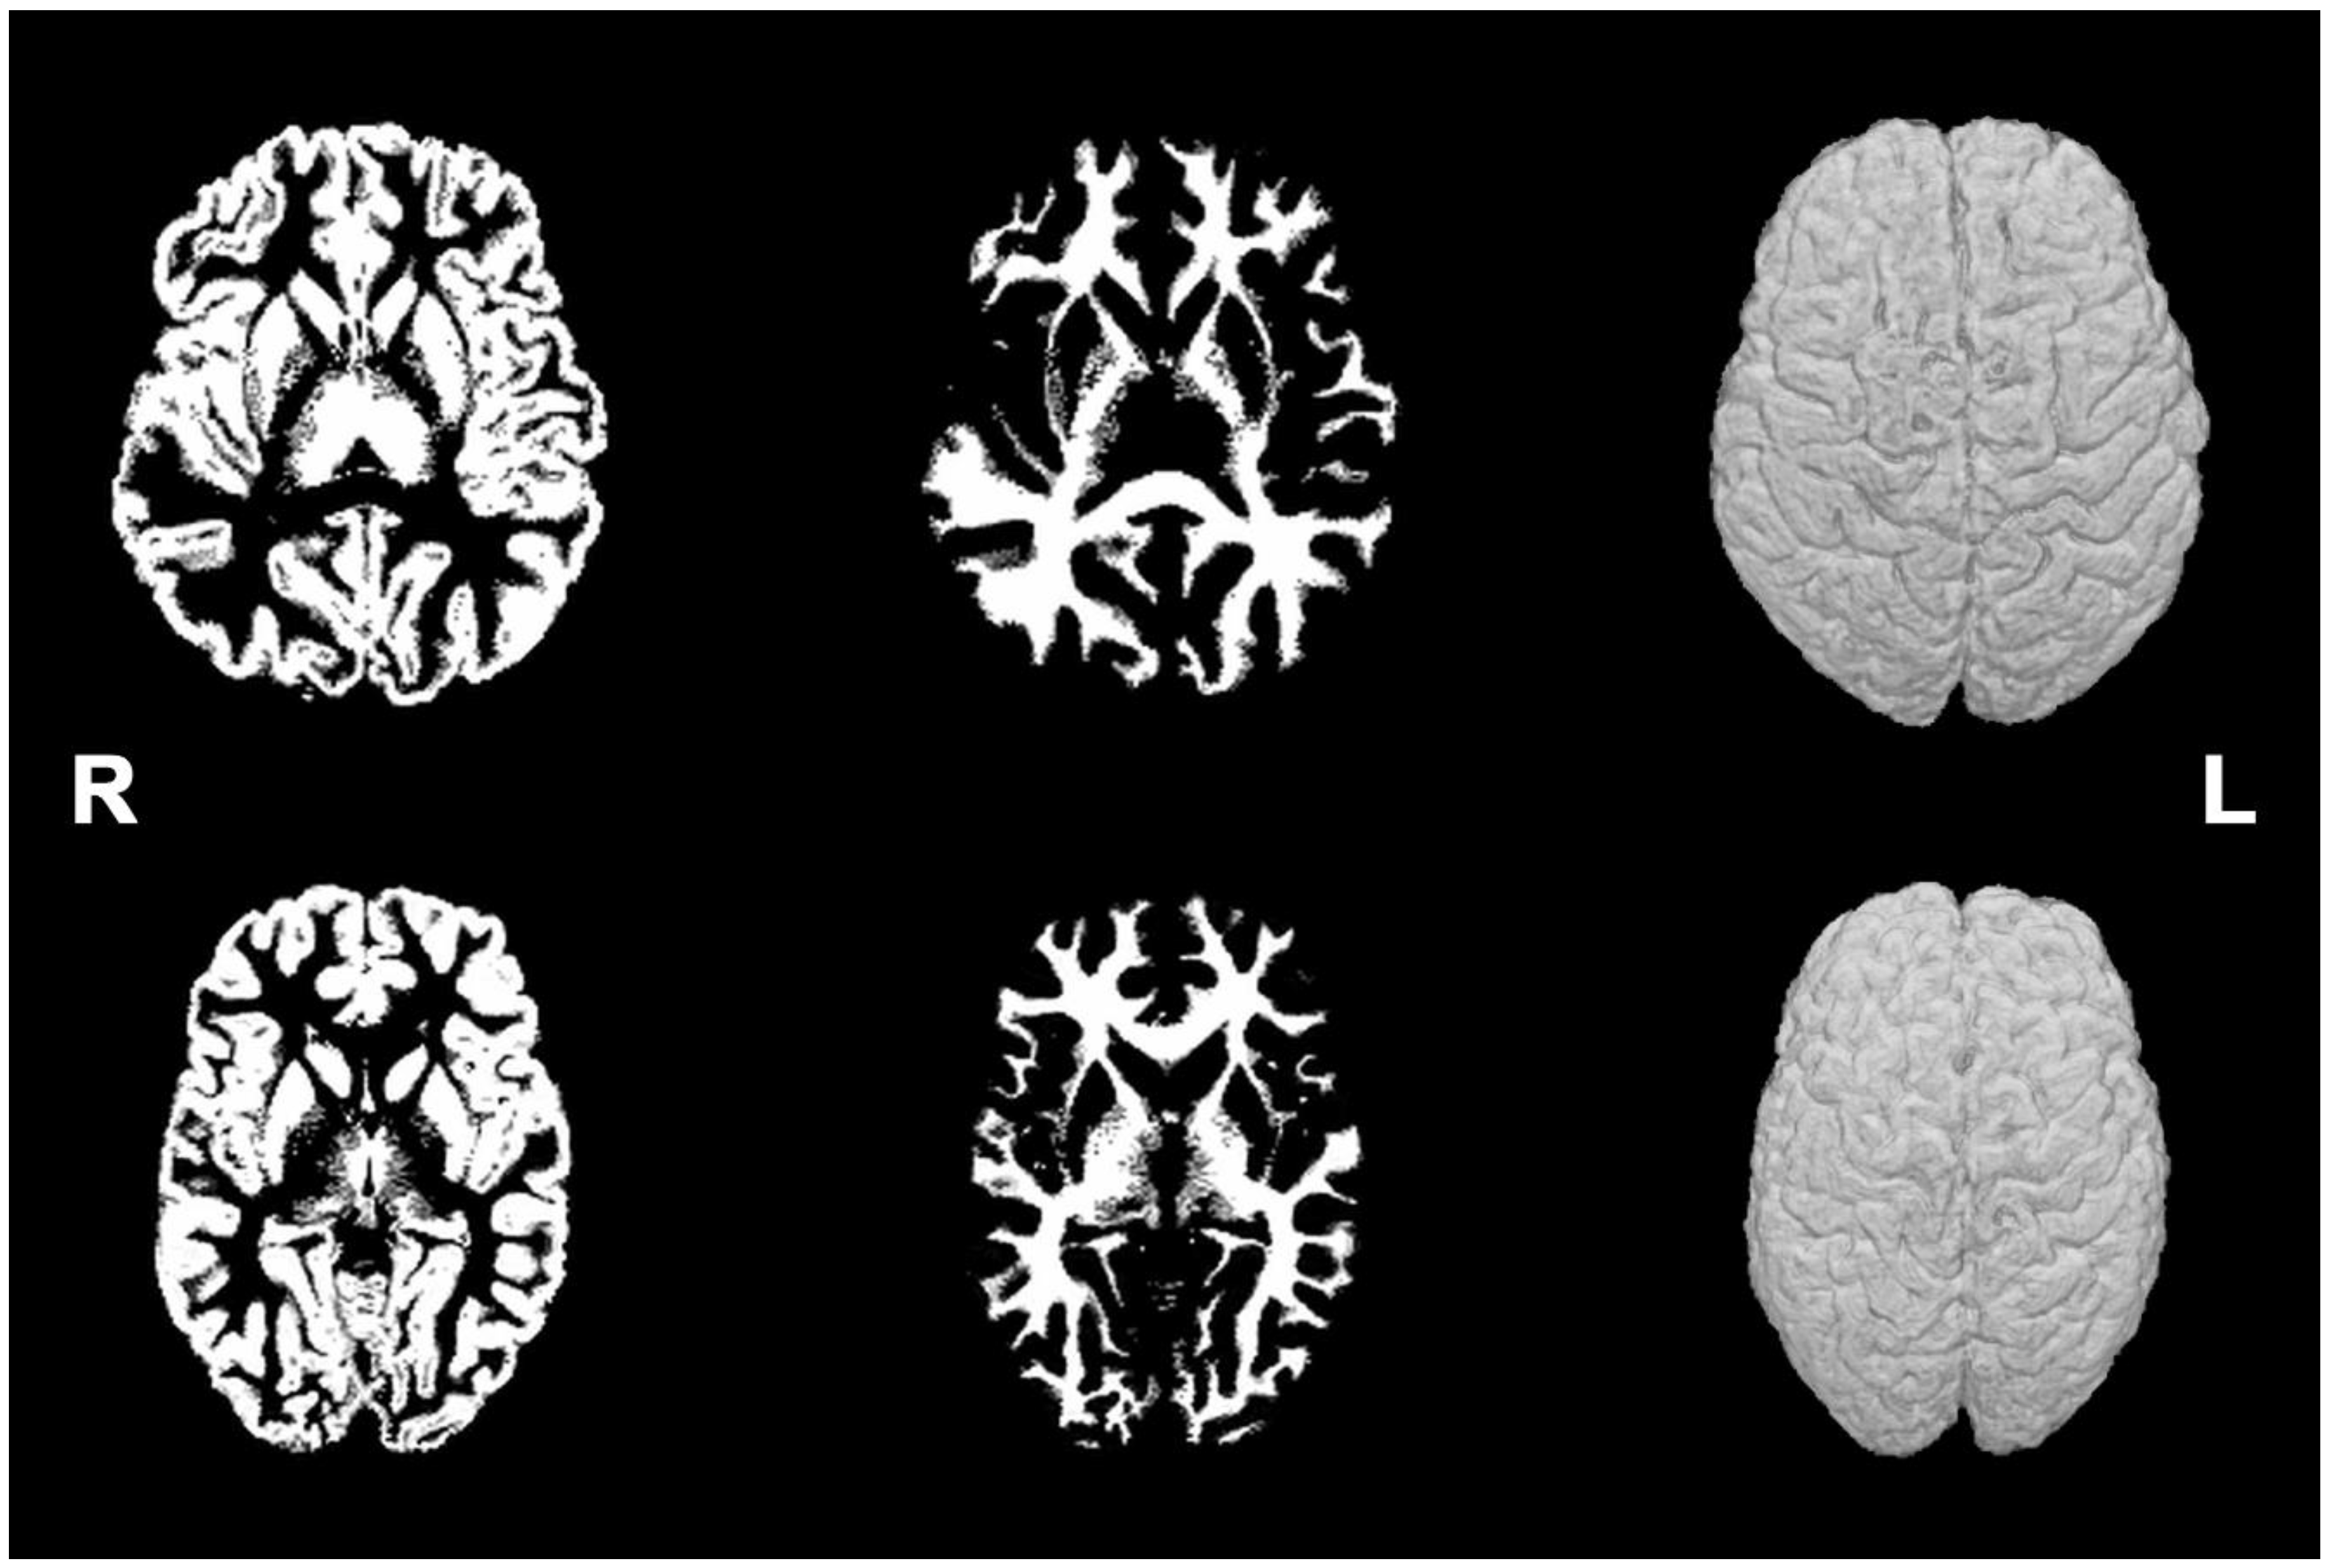

3.1. Brain MRI Phenotypes